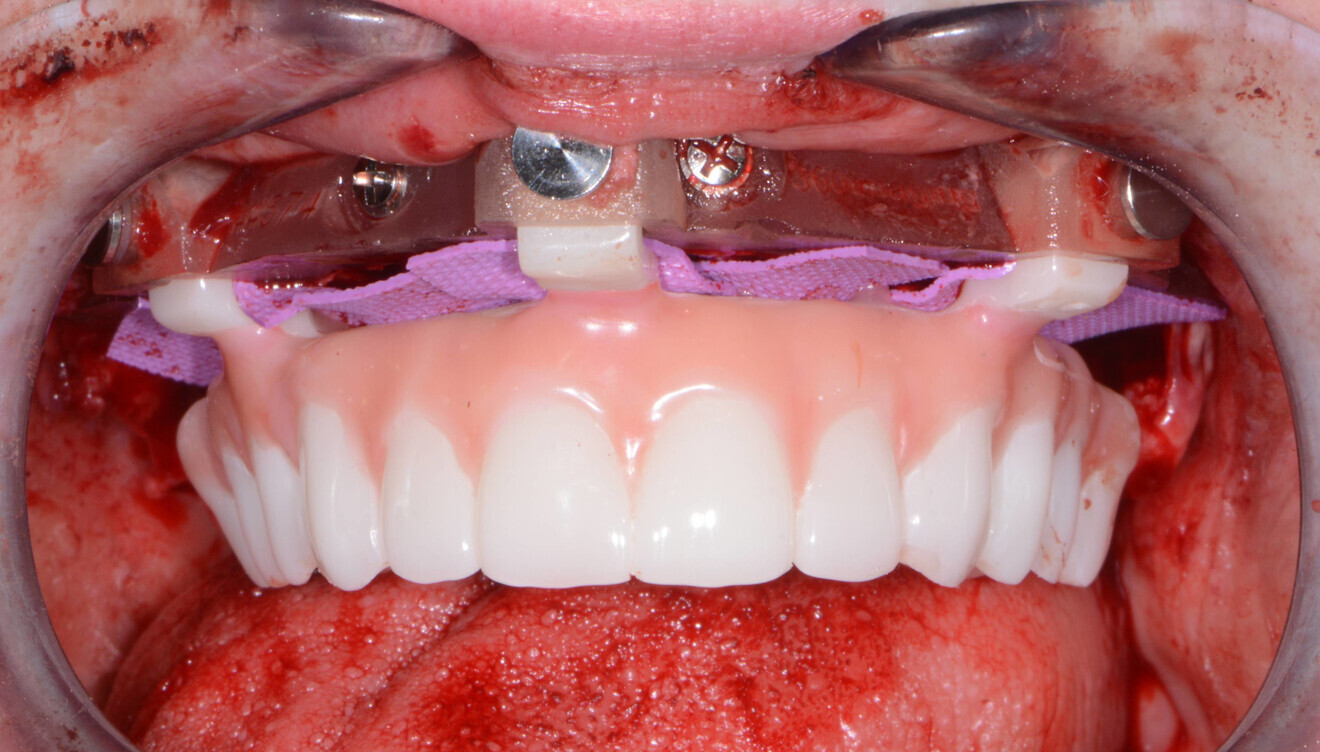

The maxillary provisional restoration was tried in to verify a passive fit over the temporary abutments. Once fit had been confirmed, trimmed dental dam pieces (COLTENE) were placed to avoid the restoration (Fig. 11) locking on during the relining procedure with REBASE III FAST hard relining material (Tokuyama Dental). After the material had polymerised, the immediate provisional restoration was removed and excess material was removed with the Torque Plus laboratory handpiece (Aseptico) and an acrylic bur (Komet). Once trimmed and polished, the provisional restoration was seated and tightened with a torque wrench to 15 N cm (Fig. 12). The access openings were filled in three-quarters of the way with PTFE tape, followed by Cavit filling material (3M ESPE).

Fig. 11: Maxillary provisional restoration positioned on the guide.

Fig. 12: Maxillary provisional restoration in situ.